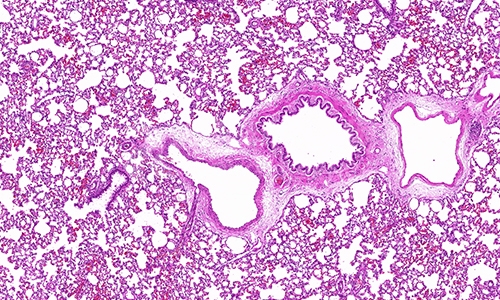

在病理学领域,HE染色(Hematoxylin and Eosin Staining)作为一种经典的染色方法,被广泛应用于组织样本的观察和分析。HE染色不仅为病